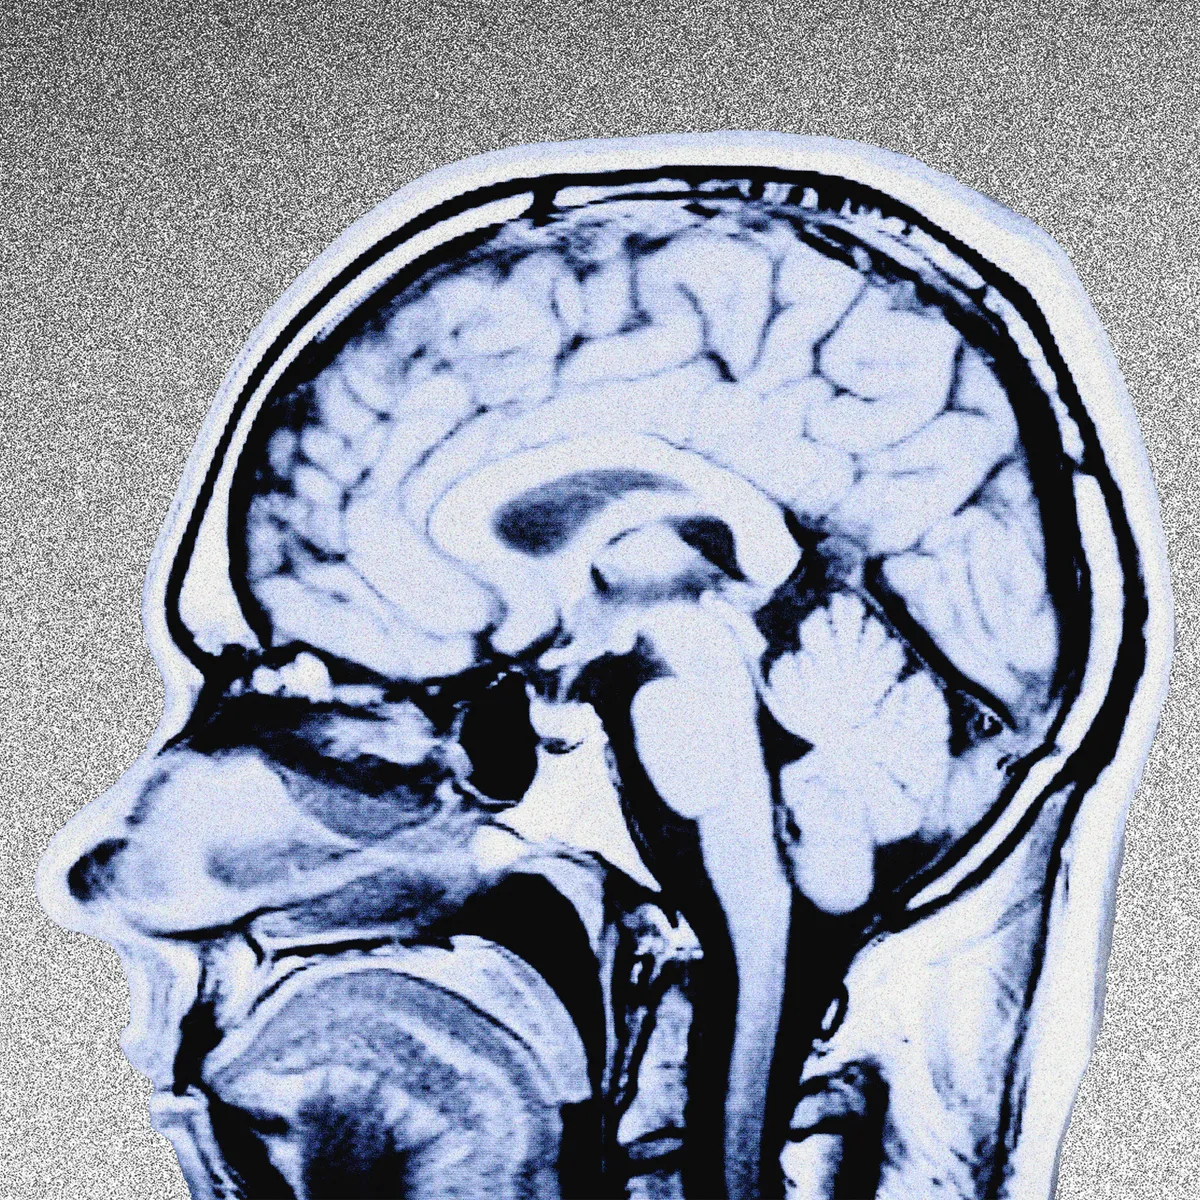

وقال بلينكن أن الضحايا الذين اصيبوا بهذا المرض تتم رعايتهم منذ تشرين الاول ٢٠٢١، في مستشفى جامعة جونز هوبكنز، مشيراً أن بعض الدبلوماسيين يخضعون الآن لفحوصات عصبية وسمعية وطب العيون متعمقة قبل مغادرتهم للعمل في الخارج من أجل الحصول على أساس للمقارنة إذا أبلغوا لاحقًا عن حادث صحي غير طبيعي.